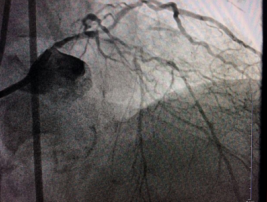

旋磨術(shù)手術(shù)中

血管內(nèi)超聲+冠脈旋磨術(shù)發(fā)揮妙用 ???解除老人3年“心痛”頑疾

入院后兩周,袁小蓉帶領(lǐng)冠脈介入團(tuán)隊(duì)經(jīng)過精心準(zhǔn)備后,對陳大爺施行了最先進(jìn)的冠脈血管內(nèi)超聲檢查術(shù)+冠脈內(nèi)膜斑塊旋磨術(shù)。

術(shù)前,介入專家首先對陳大爺進(jìn)行了冠脈血管內(nèi)超聲檢查,明確血管內(nèi)結(jié)構(gòu)以及鈣化病變位置和嚴(yán)重程度。然后將帶有鉆石顆粒的高速旋磨頭送入患者血管內(nèi)的鈣化部位,在醫(yī)生的精細(xì)操作下,位于血管內(nèi)的磨頭便以每分鐘10多萬次的轉(zhuǎn)速開始高速旋轉(zhuǎn),根據(jù)“差異性切割”(即只針對嚴(yán)重鈣化和纖維化的病變斑塊組織而不損傷正常組織)原理,將阻塞血管的動(dòng)脈斑塊迅速磨成極其微小的顆粒,隨血液循環(huán)至血管遠(yuǎn)端并通過毛細(xì)血管床吸收。經(jīng)過幾次旋磨后,阻塞血管腔的鈣化斑塊被逐漸消除,在進(jìn)行球囊擴(kuò)張之后,在兩支血管內(nèi)順利植入四枚支架,成功開通血管,手術(shù)時(shí)間總共用時(shí)1個(gè)多小時(shí)。